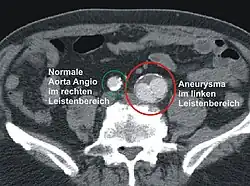

- Die Computertomografie gibt morphologisch präzise und geometrisch reproduzierbare Messwerte des Aneurysmas an. Ebenfalls können die Art der Thrombosierung, die Wandbeschaffenheit und der Bezug des Aneurysmas zu den Nachbarorganen bildlich dargestellt werden.

Als Bauchaortenaneurysma (BAA) oder abdominales Aortenaneurysma (AAA) wird eine Erweiterung der abdominalen Aorta unterhalb des Abgangs der Nierenarterien im anterioposterioren Durchmesser auf über 30 mm angesehen. Klinisch unterscheidet man zwischen asymptomatischen, symptomatischen und rupturierten Aneurysmata. Beim asymptomatischen (schmerzfreien) Aneurysma handelt es sich um einen Zufallsbefund. Beim symptomatischen Aneurysma stehen die Symptome und bei den rupturierten die Kreislaufsituation im Vordergrund.